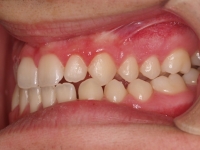

Chica de 17 años tratada en 1 año con stripping en los dientes inferiores